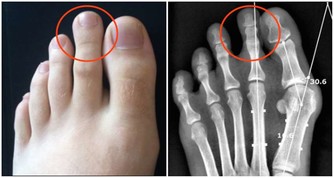

4.鼻翼長痘:

原因:與卵巢機能或生殖系統有關

改善:不要過度縱慾或禁慾,多到戶外呼吸新鮮空氣